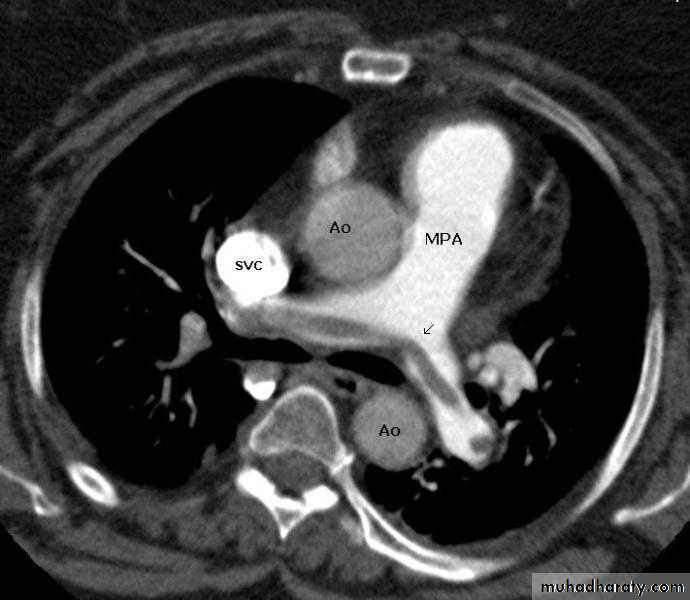

CT pulmonary angiography (CTPA)

It visualizes the distribution and extent of emboli in positive cases.

It may also prove alternative diagnosisSimultaneous visualization of femoral and popliteal veins for DVT improves sensitivity.

It is helpful in the evaluation of patients with acute circulatory collapse.

Acute right ventricular dilatation is usually present in massive PEA thrombus may be visible.

Alternative diagnosis, like heart failure and pericardial tamponade can be excluded

Echocardiography